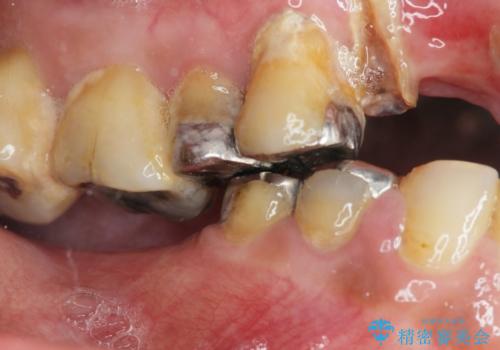

- 痛くて噛めない、これまでだましだまし治療をしてきたがこれを機にすべてきっちりと治したい、口の中の悩みを解決したいと来院されました。

抜歯や歯周病治療、欠損補綴を含め、全顎的な治療を計画・提案します。

口腔内に歯の破折や歯周病、虫歯、欠損など複数の問題が存在する場合局所的に問題を解決していくのではなく全顎的な治療を行っていくことで長期的な予後を見込むことができます。